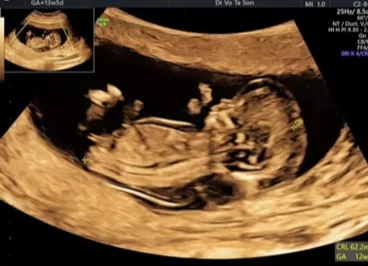

Bánh nhau - túi ối trong song thai (Chorionicity- Amnionicity)